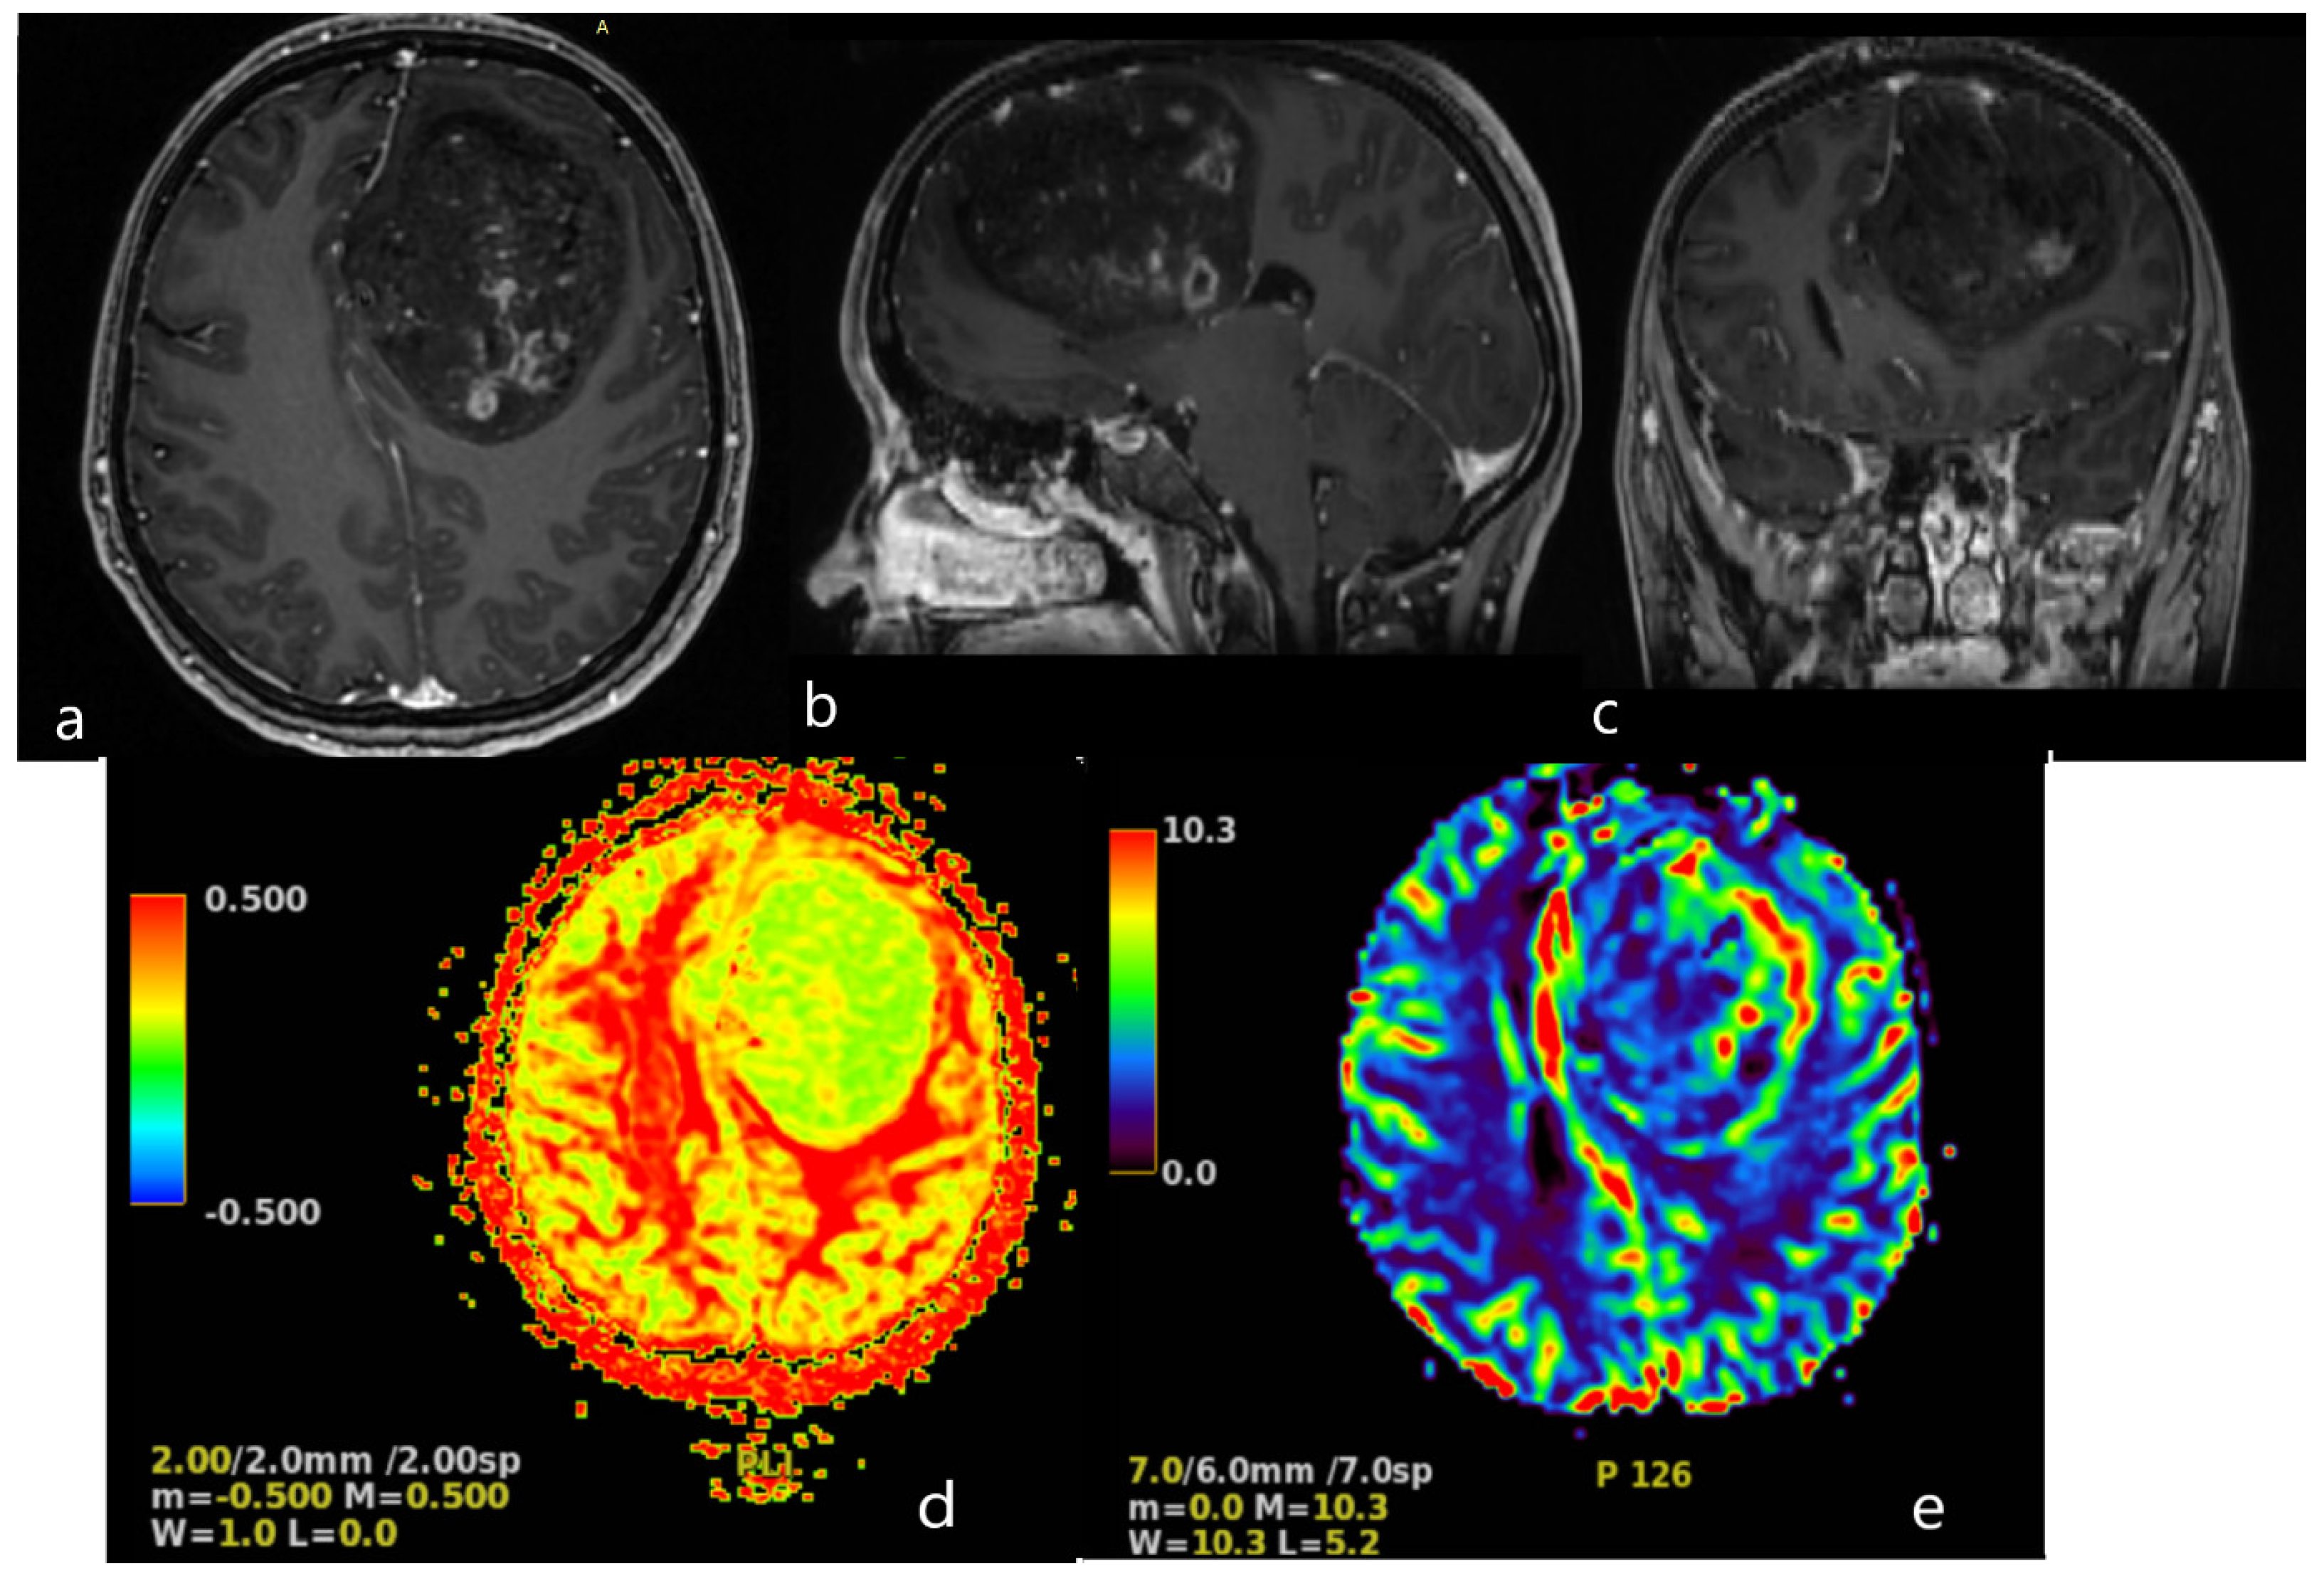

A magnetic resonance imaging (MRI) scan showed a massive (83 × 58 × 62 mm) lesion in the left frontal lobe, invading the corpus callosum, with heterogeneous hyperintense T2 and FLAIR signals, hypointensity on T1-weighted images, and peritumoral edema. After gadolinium administration, the lesion showed heterogeneous enhancement on T1-weighted imaging. The preoperative radiological diagnosis was high-grade glioma (Figure 2).

Figure 2. Brain MRI. Axial (a), sagittal (b) and frontal (c) contrast T1−weighted image demonstrates a large (83 × 58 × 62 mm) heterogeneously enhancing tumor in the left frontal lobe, results in a midine shift to the right side to 12 mm. Arterial Spin Labeled MRI Perfusion Imaging (d,e): elevated regional Cerebral blood perfusion (rCBF) and Cerebral blood volume (CBV) in lesion. Mean transit time (MTT) and Time to peak (TTP) is prolonged. MR spectroscopy (MRS): elevated choline/creatine peaks.